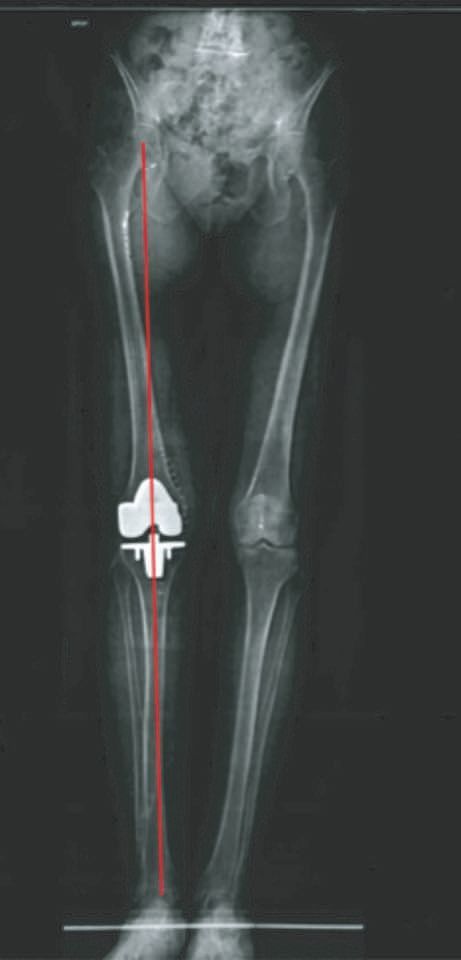

Actualité Intérêt des guides de coupe sur mesure après une planification preoperatoire scanner 3d dans la mise en place d’une prothèse totale de genou , Gilles Pasquier Service de Chirurgie orthopédique, CHU de Lille, 59037 Lille, France 🖂 gilles.pasquier@chu-lille.fr , J.-P. Franceschi : CCOS Mérignac ° : Institut de l'appareil locomoteur Nollet, Paris , Abdou Sbihi Centre Borely-Mermoz, Hôpital de la Conception, Marseille, France , Vincent Leclercq Symbios Orthopédie SA, Lausanne, Suisse , J. Plé Avenue des Sciences, Yverdon les Bains, CH-1400 N°218 - Cahier 2 - Novembre 2012 ● 23 min de lecture